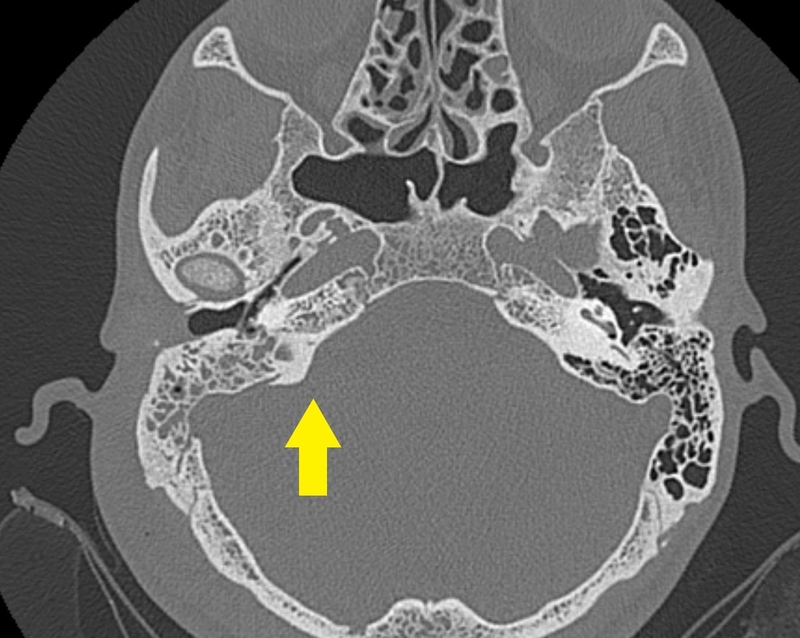

/https://cms-prod.s3-sgn09.fptcloud.com/viem_tai_xuong_chum_man_tinh_trieu_chung_cach_dieu_tri1_334c6832ba.jpg) Hình ảnh chụp khối viêm tai xương chũm

Hình ảnh chụp khối viêm tai xương chũmTriệu chứng của viêm tai xương chũm

Khi mắc chứng viêm tai xương chũm mãn tính, người bệnh nên đến các cơ sở y tế để được thực hiện những phương pháp chẩn đoán. Theo đó, phương pháp cận lâm sàng có tác dụng hỗ trợ chẩn đoán bệnh đó là chụp X - quang. Bác sĩ sẽ dùng 2 phim là phim Schuller để có thể quan sát vùng xương chũm bị mờ đều, một số tế bào nhỏ ăn thông với nhau, vách ngăn của tế bào bị bào mòn. Chụp phim Chausse III có thể làm xuất hiện tiêu hủy xương con, làm rò ống bán khuyên ngoài và mất cựa ở sau trên nhĩ. Bên cạnh đó, phương pháp chụp cắt lớp tai cũng được áp dụng để chẩn đoán chính xác căn bệnh viêm tai xương chũm mạn tính.

- Chụp CT xương thái dương để theo dõi hình ảnh đọng dịch và mất thông bào.